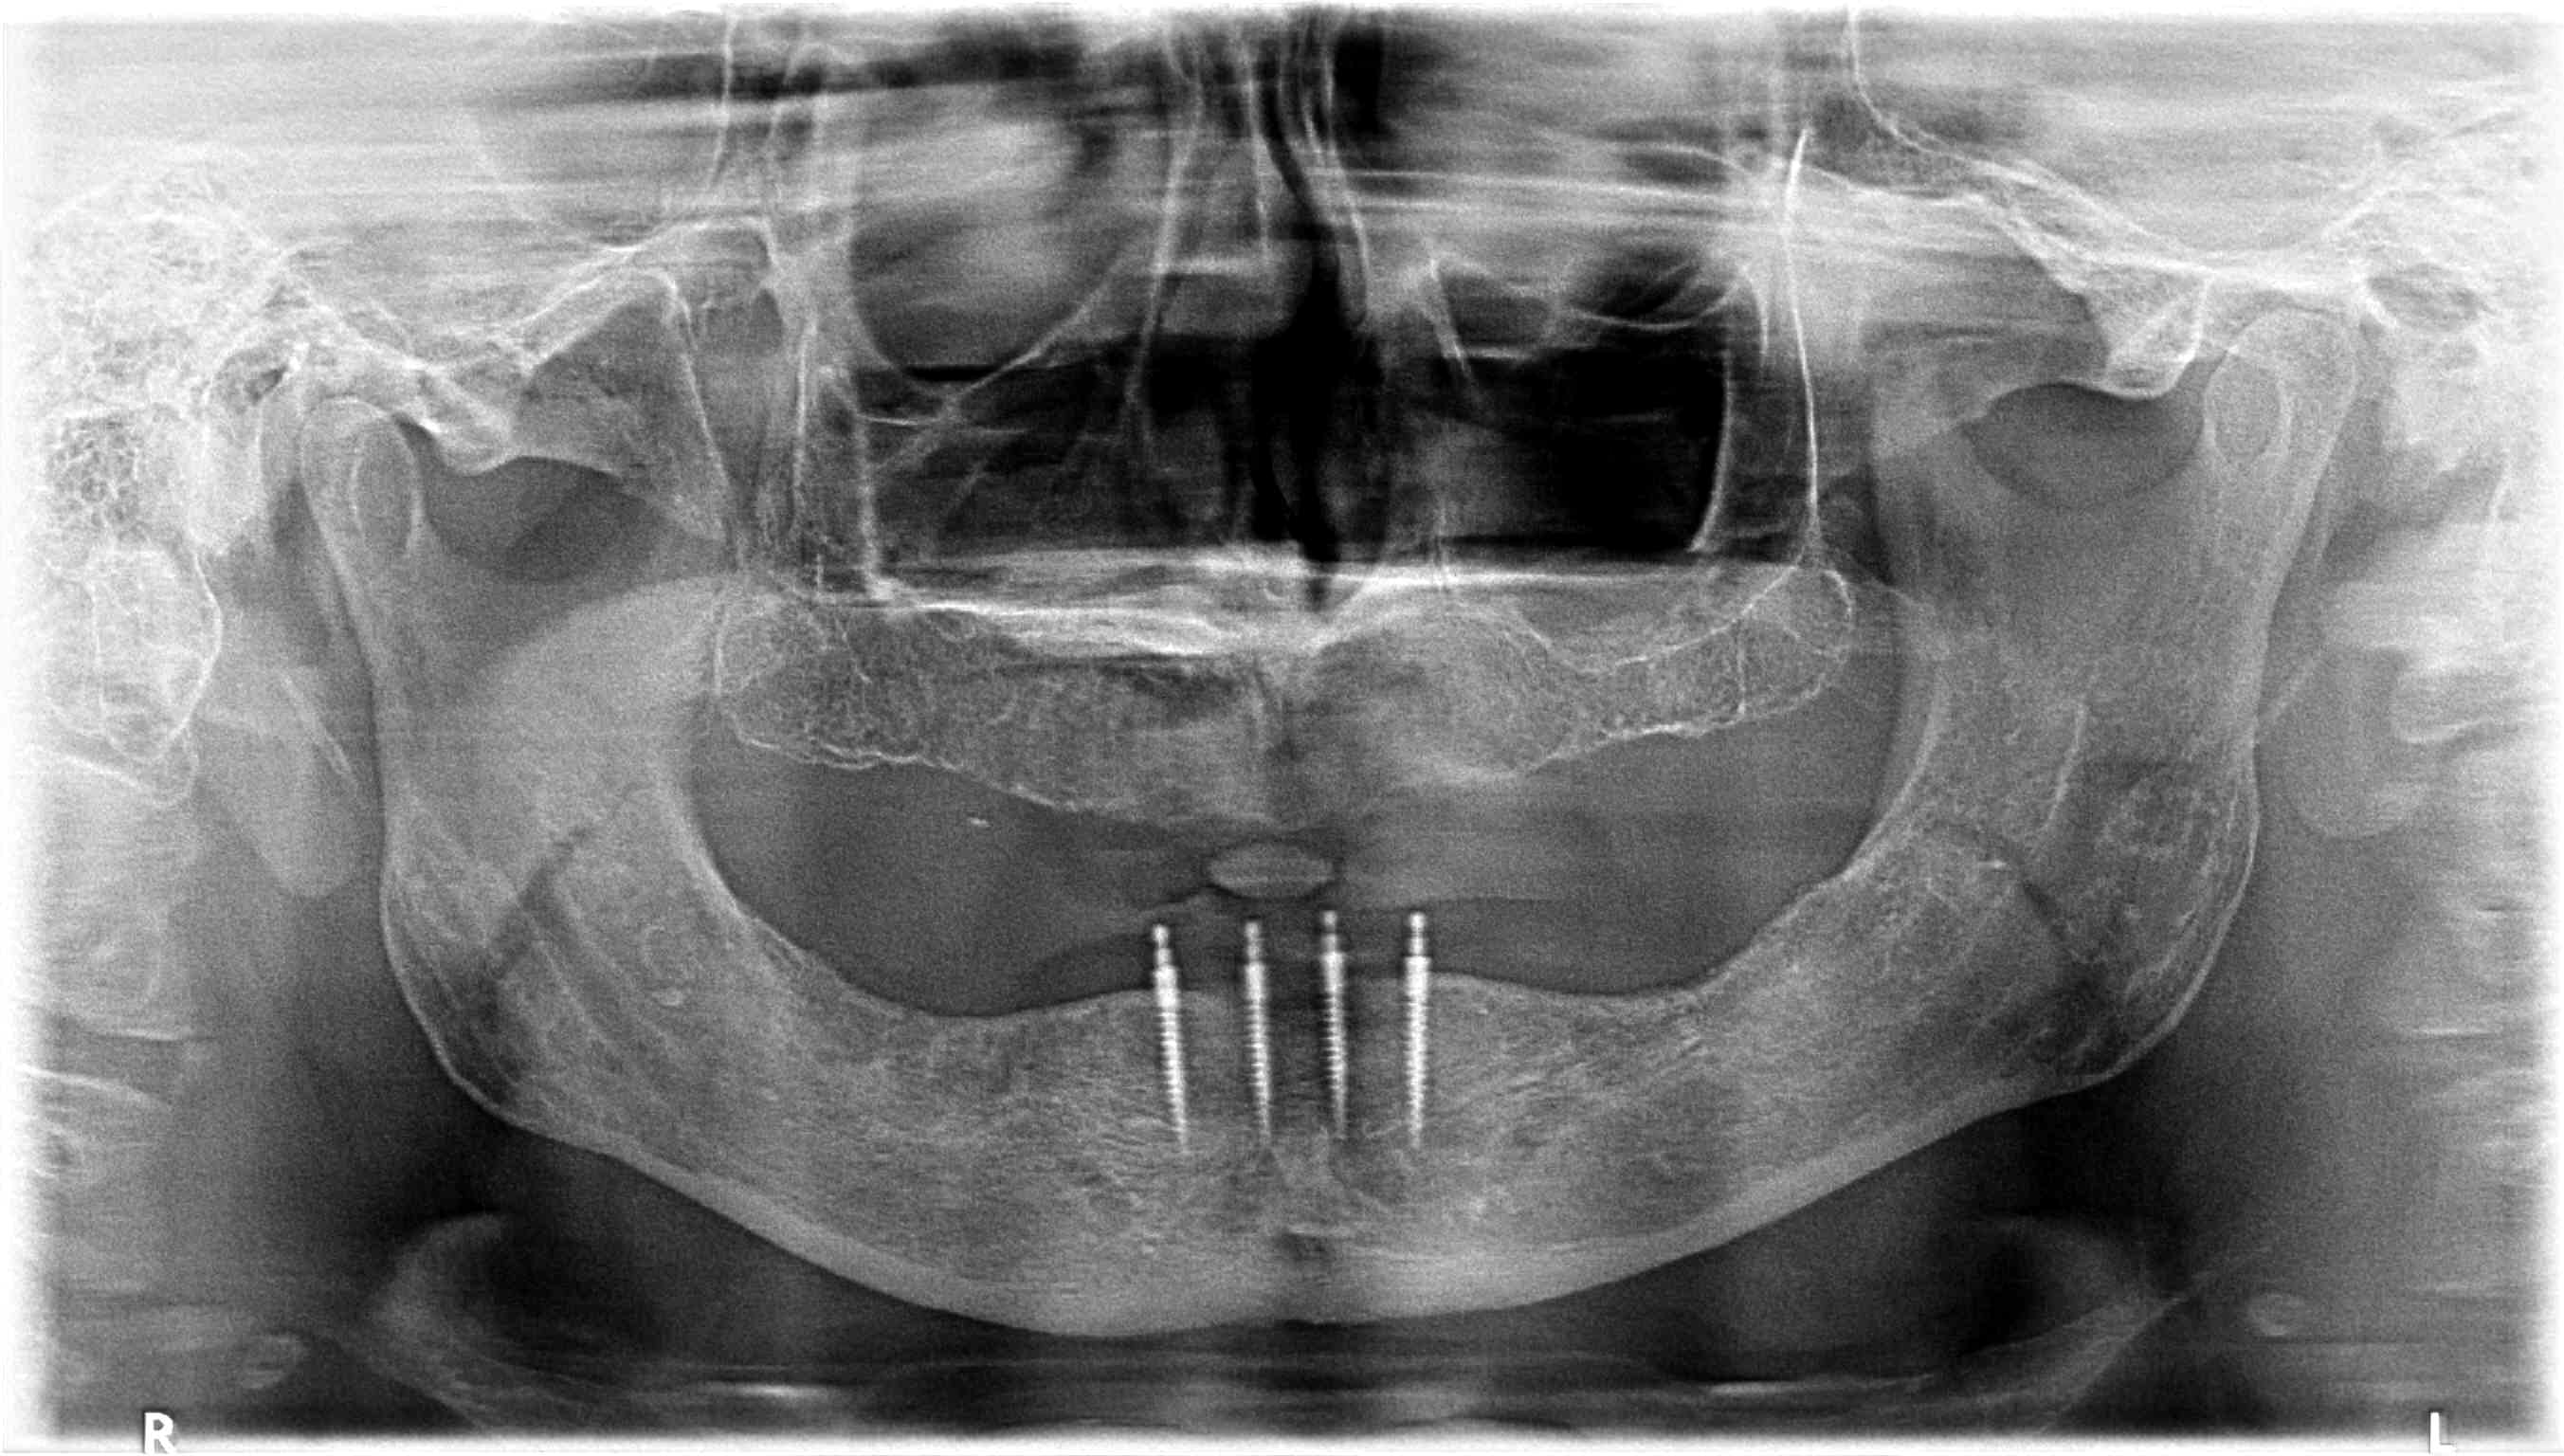

A panoramic radiograph was taken at the start of the consultation appointment. The radiograph revealed an edentulous maxilla and mandible with no remarkable pathology. Bone height was generally good and well suited for the placement of implants. The anterior mandible would serve as a suitable site for four mini implants. The panoramic radiograph served as a screening tool, which could be used to develop the early stages of an implant treatment plan at a consultation.

Fig 9. Postoperative radiograph showing successful implant placement.

Figure 9